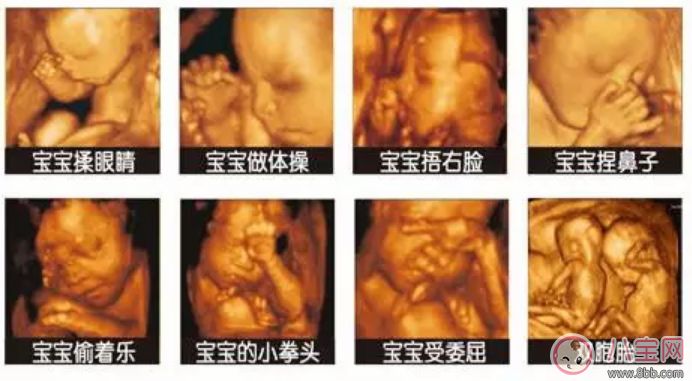

1、傳統的B超只能簡單的觀察到胎兒的四肢是否健全和模糊的胎兒動態,但是四維彩超檢查,能清晰的觀察到寶寶在媽媽肚子里的即時動態和各種神態,還能立體清晰的看到妊娠中晚期胎兒的全貌,更能檢測到寶寶的四肢和內臟發育情況。